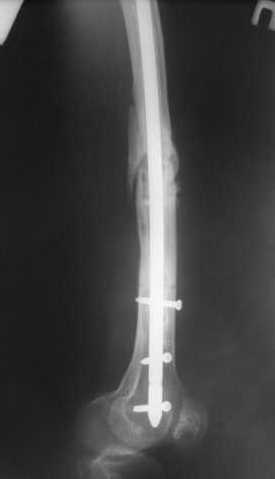

Как обещал, выкладываю рентгенограммы нашего пациента.

Пациенту М., 30-ти лет, 1,5 года назад в одной из московских больниц был выполнен остеосинтез бедренной кости штифтом UFN (диаметр штифта 9 мм).

К нам больной поступил с признаками ложного сустава бедренной кости, перелома

штифта и дистального блокирующего винта (images 1,2,3).

27 марта выполнено удаление блокирующих винтов (сломанный винт пришлось высверливать цапфен-бором), сломанного штифта (дистальный фрагмент удален через канал, образованный разверткой из коленного сустава - image 4),

рассверливание костно-мозгового канала, реостеосинтез штифтом UFN (при проведении штифта в дистальном отломке мы использовали поляризующий винт, диаметр штифта 10 мм). После операции в связи гемартрозом дважды (на 1 и 3 сутки) выполняли пункцию коленного сустава. Сейчас признаков скопления жидкости в полости сустава нет. Послеоперационные рентгенограммы - images 5, 6, 7.